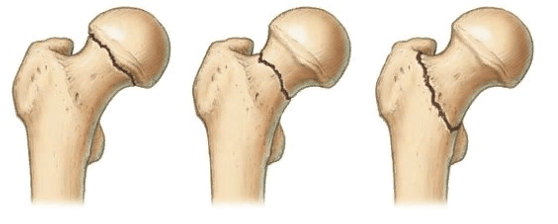

Локализация наиболее распространенных переломов.

При развитии травм бедренной кости большую их часть составляют повреждения в зоне шейки, в том числе на фоне возрастных изменений. В большинстве случаев при переломах страдает вертельная часть, и крайне редко - подвертельная. Кроме того, перелом в зоне шейки бедра - внутрисуставной, поэтому раннее лечение просто необходимо. Практически никогда такой перелом не заживает самостоятельно, без точного восстановления анатомической целостности кости внутри сустава. Поэтому такая травма - это один из основных показаний к операции. Кроме того, необходимо оперативное лечение в случае:

- Перелом верхней части бедра. Включает медиальные внутрисуставные переломы: субкапитальные, трансцервикальные, базальные. К этой группе относят и переломы шейки. Медиальные травмы могут быть аддукционными - приводящими к расширению шеечно-диафизарного угла, либо вызывать уменьшение угла. Последние именуются абдукционными или вальгусными. К этой группе относят вертельные переломы, затрагивающие верхнюю часть бедра. Это межвертельные, чрезвертельные повреждения, а также переломы большого или малого вертела (изолированные травмы вертелов).